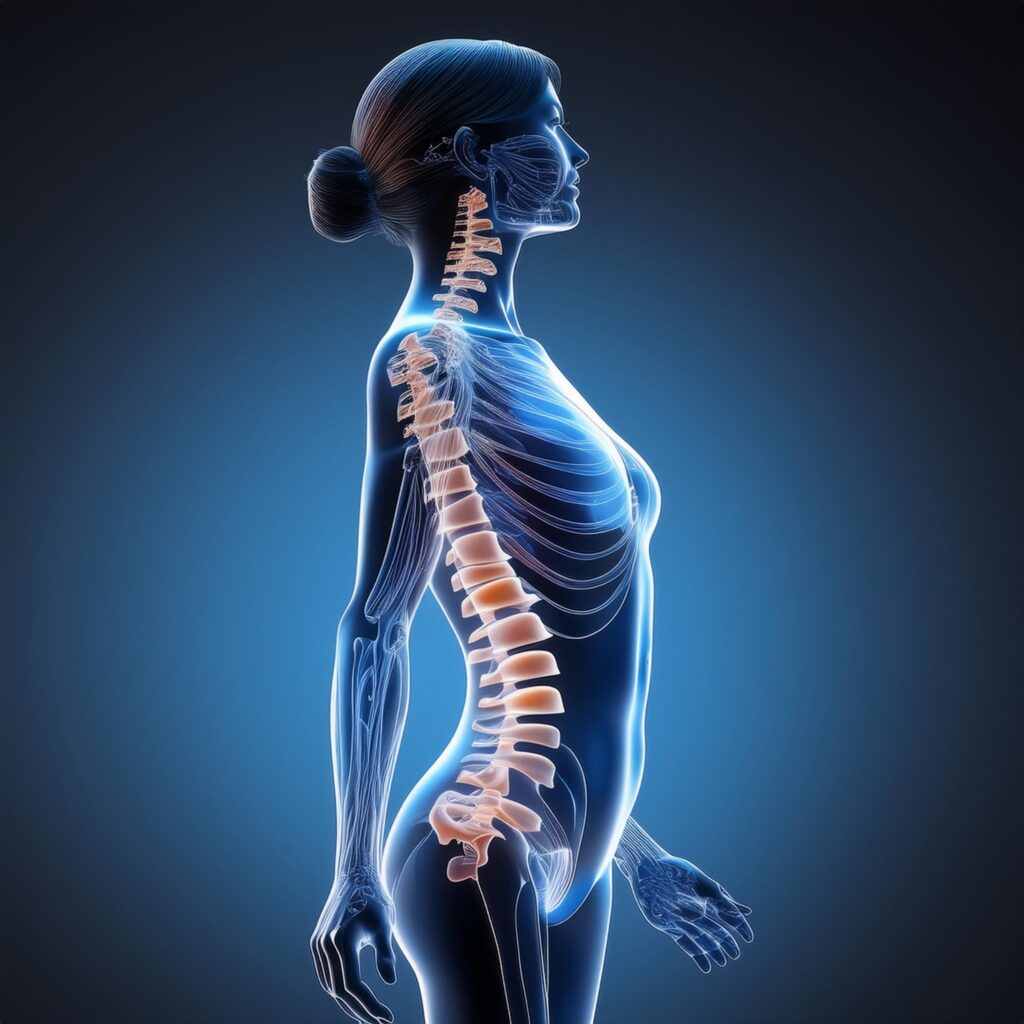

腰痛の原因は人によってさまざまですが、多くの場合は姿勢の崩れと体幹の筋力低下が大きく関係しています。特に現代では、デスクワークやスマートフォンの使用時間が増え、同じ姿勢を長時間続ける生活が一般的になっています。

このような生活習慣が続くと、骨盤や背骨のバランスが崩れ、腰に負担がかかりやすい状態になります。また、身体を支えるインナーマッスルが弱くなると、腰回りの筋肉だけで身体を支えることになり、慢性的な腰痛につながることも少なくありません。

ピラティスは、身体の中心である体幹(コア)を意識しながら動くエクササイズです。特に腹部・背中・骨盤周りの筋肉をバランスよく使うため、腰に過剰な負担がかかりにくい身体づくりを目指すことができます。例えば、腹筋や背筋だけを鍛えるトレーニングとは違い、ピラティスでは 深層筋(インナーマッスル) を意識して身体を安定させる動きが中心になります。このインナーマッスルがしっかり働くことで、背骨や骨盤の安定性が高まり、腰への負担を減らすことができます。

ピラティスの大きな特徴は、身体の深い部分にあるインナーマッスル(体幹の筋肉)を鍛えられることです。インナーマッスルは、背骨や骨盤を安定させる役割を持ち、身体のバランスを保つためにとても重要な筋肉です。この筋肉が弱くなると、身体を支える力が不足し、腰の筋肉だけで身体を支える状態になります。その結果、腰の筋肉に負担が集中し、慢性的な腰痛につながることがあります。

腰痛の原因のひとつに、骨盤や背骨のバランスの乱れがあります。骨盤は身体の土台の役割を持っているため、この部分が傾いたりねじれたりすると、背骨にも影響が出てしまいます。ピラティスでは、骨盤や背骨の位置を意識しながら身体を動かすエクササイズが多く取り入れられています。そのため、身体の中心を安定させながら筋肉を使うことができ、腰に負担の少ない身体の使い方を身につけることができます。

腰痛の大きな原因のひとつが姿勢の崩れです。猫背や反り腰の状態が続くと、腰の筋肉に余計な負担がかかり、痛みや違和感につながることがあります。ピラティスでは背骨の動きや骨盤の位置を意識しながらエクササイズを行うため、自然と正しい姿勢を保つ感覚が身についていきます。姿勢が整うことで、腰への負担が軽減され、腰痛の予防にもつながります。